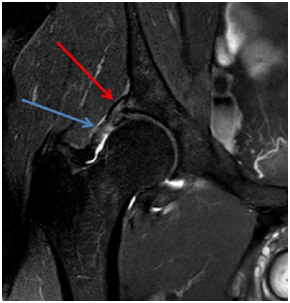

MRI shows injury of the superolateral aspect of the acetabular labrum, acetabular, femoral head and neck edema, joint effusion and partial tear of the iliofemoral ligament (Figures 1-3).

Figure 2 MRI in T1 sequence in the coronal section demonstrating labral lesion (red arrow) and partial rupture of the iliofemoral ligament (blue arrow).